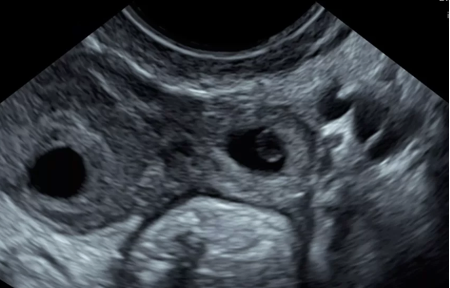

Pelvic / GU / ObGyn

Renal

Abdominal